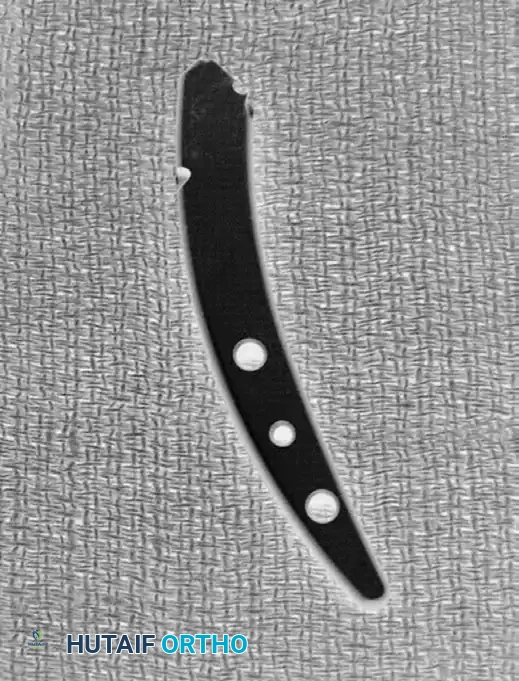

6. Internal Fixation

Stabilize the osteotomy and the intercalary graft using a robust volar plate. Historically, a 3.5-mm angled T-shaped plate was utilized, though modern anatomically contoured volar locking plates are now frequently employed.

💡 Clinical Pearl: Correcting Pronation Deformity

Distal radius malunions frequently feature a supination deformity of the shaft relative to a pronated distal articular fragment. When the flat surface of a rigid volar plate is applied and compressed to the volar aspect of the radius, it inherently acts to derotate the distal fragment, effectively correcting the pronation deformity.